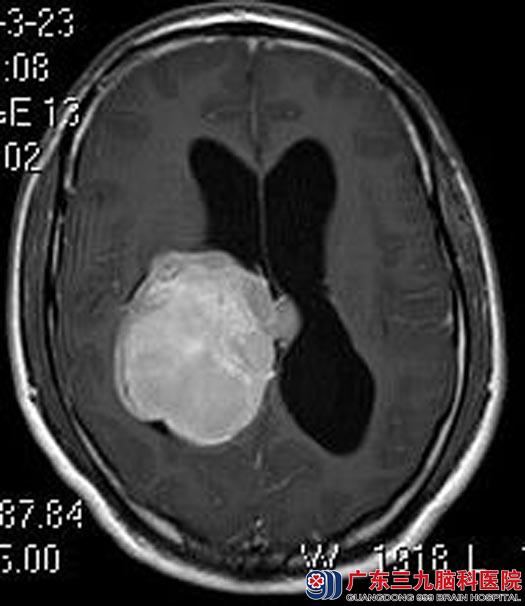

去年,邱先生出现四肢乏力、呃逆、步态不稳等,检查发现右侧丘脑、脑室内巨大占位并梗阻性脑积水,次日即就诊于广东三九脑科医院,头颅磁共振检查提示:右侧侧脑室三角区占位性病变,大小约60.8mm×63.2mm×57.6mm,考虑脑膜瘤可能性大。由综合神经外科鲁明主任主刀将肿瘤全切。

▲手术前